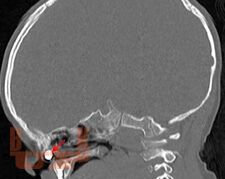

Методические рекомендации позволяют студентам, проходящим цикл практических занятий по оториноларингологии, приобрести знания по оказанию неотложной помощи в оториноларингологии.

Методическое пособие предназначено для студентов, обучающихся по специальностям Педиатрия, Лечебное дело и Стоматология, в котором представлены различные виды часто встречающейся острой патологии со стороны ЛОР органов, рассмотрены методы ее диагностики и различные способы оказания неотложной помощи больным.